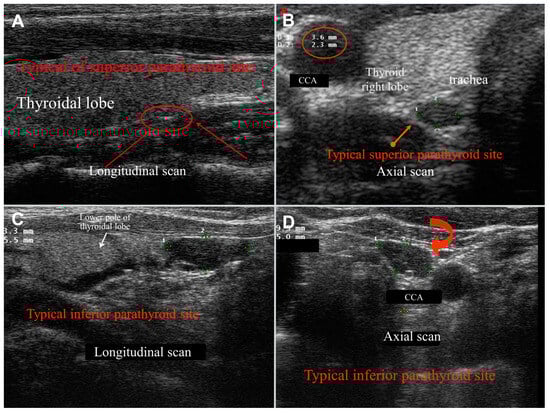

Figure 1. Typical US features and location of superior ((A): normal; (B): adenoma) and inferior ((C): normal; (D): adenoma) parathyroids. Superior glands are usually located posteriorly to the third medium of the thyroid lobes, while inferior ones are normally positioned just inferiorly to the lobe poles. The common carotid artery (CCA) represents an important landmark when exploring the thyroid compartment, and inferior parathyroid glands can be often seen along the CCA sheath (as in (D)). Parathyroid glands usually present hypoechoic structure and oval shape; one or more glands can be defined as enlarged when the longest diameter measures more than 0.6 cm.

During US examinations, abnormal (pathological) parathyroid glands appear as well vascularized parenchymatous solid masses, very rarely exceeding 3 cm in size. They typically appear hypoechoic compared to the thyroid, exhibiting sharp, regular edges, occasionally with curvilinear features, and seldom containing fluid (Figure 1).

While laboratory tests form the basis of diagnosis, imaging plays a crucial role in localizing parathyroid tumors for precise surgical planning. Normal parathyroid glands are minute, measuring approximately 6 mm in length and 3.5 × 1.5 mm in width, with a flat morphology. They are typically located within the visceral space of the neck, posteriorly or immediately distally to the thyroid lobes and much more rarely within thyroid lobes or ectopically in the mediastinum. Superior parathyroid glands maintain a relatively consistent position, often posterior to the middle third of the thyroid lobes; those with an increased dimension tend anyway to reach the lower pole of the lobes deeper than the thyroid. In contrast, the location of inferior parathyroid glands is more variable, with the majority located caudal and posterior or lateral to the inferior pole of the thyroid lobes. However, they may also be intrathyroidal or within the cervical thymus. They are usually located in a superficial plane right behind the superficial layer of the cervical fascia [4].